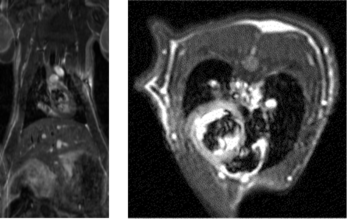

- マウスの癌における血管新生の様子

約5mm程の癌の血管透過性マッピング

青>黄>赤>白 の順に透過性が大きくなっています。 - 脳梗塞ラットのfMRI